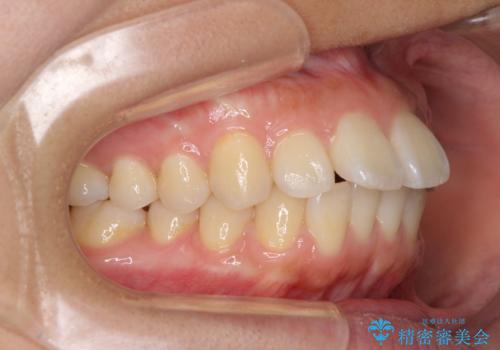

前に出ている前歯を引っ込めたい インビザライン矯正

- 前方に傾斜した上下の前歯を気にして来院された患者様です。

唇の閉じにくさや横顔のシルエットが気になるような突出感ではなかったため、インビザラインを用いて、歯列の遠心移動とIPR(歯と歯の間を削る)により前歯の傾斜を改善していくこととしました。

スムーズに終了すると思われましたが、インビザライン矯正独特の奥歯が咬み合わない状態が続き、更には遠方へ転居されたこともあり、治療期間は長引いてしまいました。